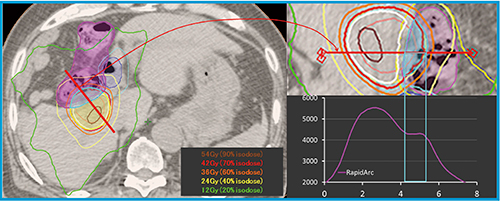

図4 肝細胞がんに対するSBRTの線量分布の一例(十二指腸,大腸近接例) 大船中央病院では,消化管近傍の肝細胞がんに対して42Gy/14回の分割照射を行っている。処方法としては,消化管PRVとPTVが重複する領域は42Gyに抑えつつ,重複しない領域に対しては70% isodose曲線と一致させるようにしている。また,消化管PRVの最大線量は50Gyを超えないことにしている。左図の赤線の線量プロファイルを右図に示している。RapidArcを用いることにより,消化管PRVとPTV重複領域への線量を42Gyに抑えつつ,重複しない領域への線量が増加している。また,消化管では可及的に線量が抑えられている。このように,RapidArcは放射線治療医の要求に応じた線量分布を作成可能にしている。 大腸(○),十二指腸(○),PTV(○)。等線量曲線は外側より12Gy(○),24Gy(○),36Gy(○),42Gy(○)(処方線量),54Gy(○)。